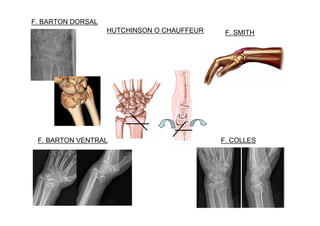

7.1 Fracturas decúbito y radio distal -1/6 de todas las fracturas del cuerpo y el 90% de ellas son Colles. -Tres picos de edad: -Niños 5-14 años -Varones Jóvenes < 50ª. -Mujeres > 40 osteoporosis. Fracturas de radio: -Fracturas de Colles -Fracturas de Smith -Barton -Rean Barton -Hutchinson o Chauffeur.

F. COLLES F. SMITH F.BARTON VENTRAL HUTCHINSON O CHAUFFEUR F. BARTON DORSAL

• TRATAMIENTO: • Adulto: –No desplazada: yeso braquiopalmar a 90º. Citar a CEX Traumatología en una semana. – Desplazada: • Reducción cerrada e inmovilización con yeso. • Reducción abierta y osteosíntesis. • Niño: – Rodete (región metafisaria): yeso o férula antebraquial. Citar en CEX Traumatología. – Tallo verde: yeso braquiopalmar a 90º. Citar en CEX Traumatología. – Fractura completa o inestable: reducción +/- osteosíntesis